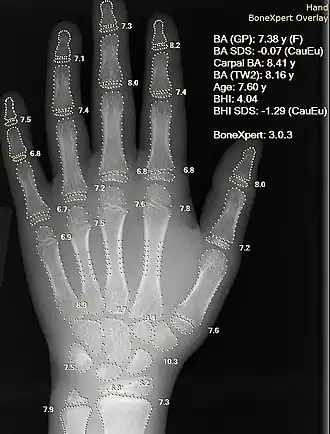

AI in healthcare is often used for classification, to evaluate a CT scan or electrocardiogram or to identify high-risk patients for population health. AI is helping with the high-cost problem of dosing. One study suggested that AI could save $16 billion. In 2016, a study reported that an AI-derived formula derived the proper dose of immunosuppressant drugs to give to transplant patients.[187] Current research has indicated that non-cardiac vascular illnesses are also being treated with artificial intelligence (AI). For certain disorders, AI algorithms can aid in diagnosis, recommended treatments, outcome prediction, and patient progress tracking. As AI technology advances, it is anticipated that it will become more significant in the healthcare industry.[188]

The early detection of diseases like cancer is made possible by AI algorithms, which diagnose diseases by analyzing complex sets of medical data. For example, the IBM Watson system might be used to comb through massive data such as medical records and clinical trials to help diagnose a problem.[189] Microsoft's AI project Hanover helps doctors choose cancer treatments from among the more than 800 medicines and vaccines.[190][191] Its goal is to memorize all the relevant papers to predict which (combinations of) drugs will be most effective for each patient. Myeloid leukemia is one target. Another study reported on an AI that was as good as doctors in identifying skin cancers.[192] Another project monitors multiple high-risk patients by asking each patient questions based on data acquired from doctor/patient interactions.[193] In one study done with transfer learning, an AI diagnosed eye conditions similar to an ophthalmologist and recommended treatment referrals.[194]

Artificial neural networks are used as clinical decision support systems for medical diagnosis,[196] such as in concept processing technology in EMR software.